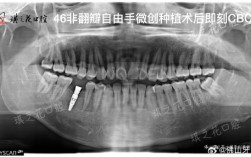

• 种牙前必须拍CT吗?这些检查到底有啥用?

种牙前必须拍CT吗?这些检查到底有啥用?

种牙前通常需要拍CT,这是确保种植手术成功、规避风险的关键步骤,虽然部分患者可能认为通过口腔检查或普通X光片即可评估种植条件,但CT的三维成像能提供普通检查无法企及的细节,直接影响种植方案的设计、手术的安全性和远期效果,以下从多个维度详细解...